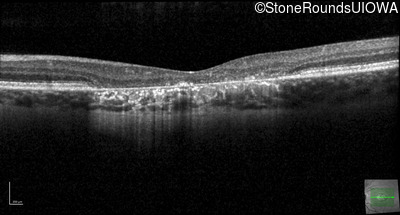

This 22 year old man had macular abnormalities noted incidentally at a routine eye exam at age 19. Since then, he has experienced a gradual loss of acuity particularly in the left eye.

| AR Stargardt Disease | ABCA4 | Tyr245Stop TAT>TAG | Unknown | AR |